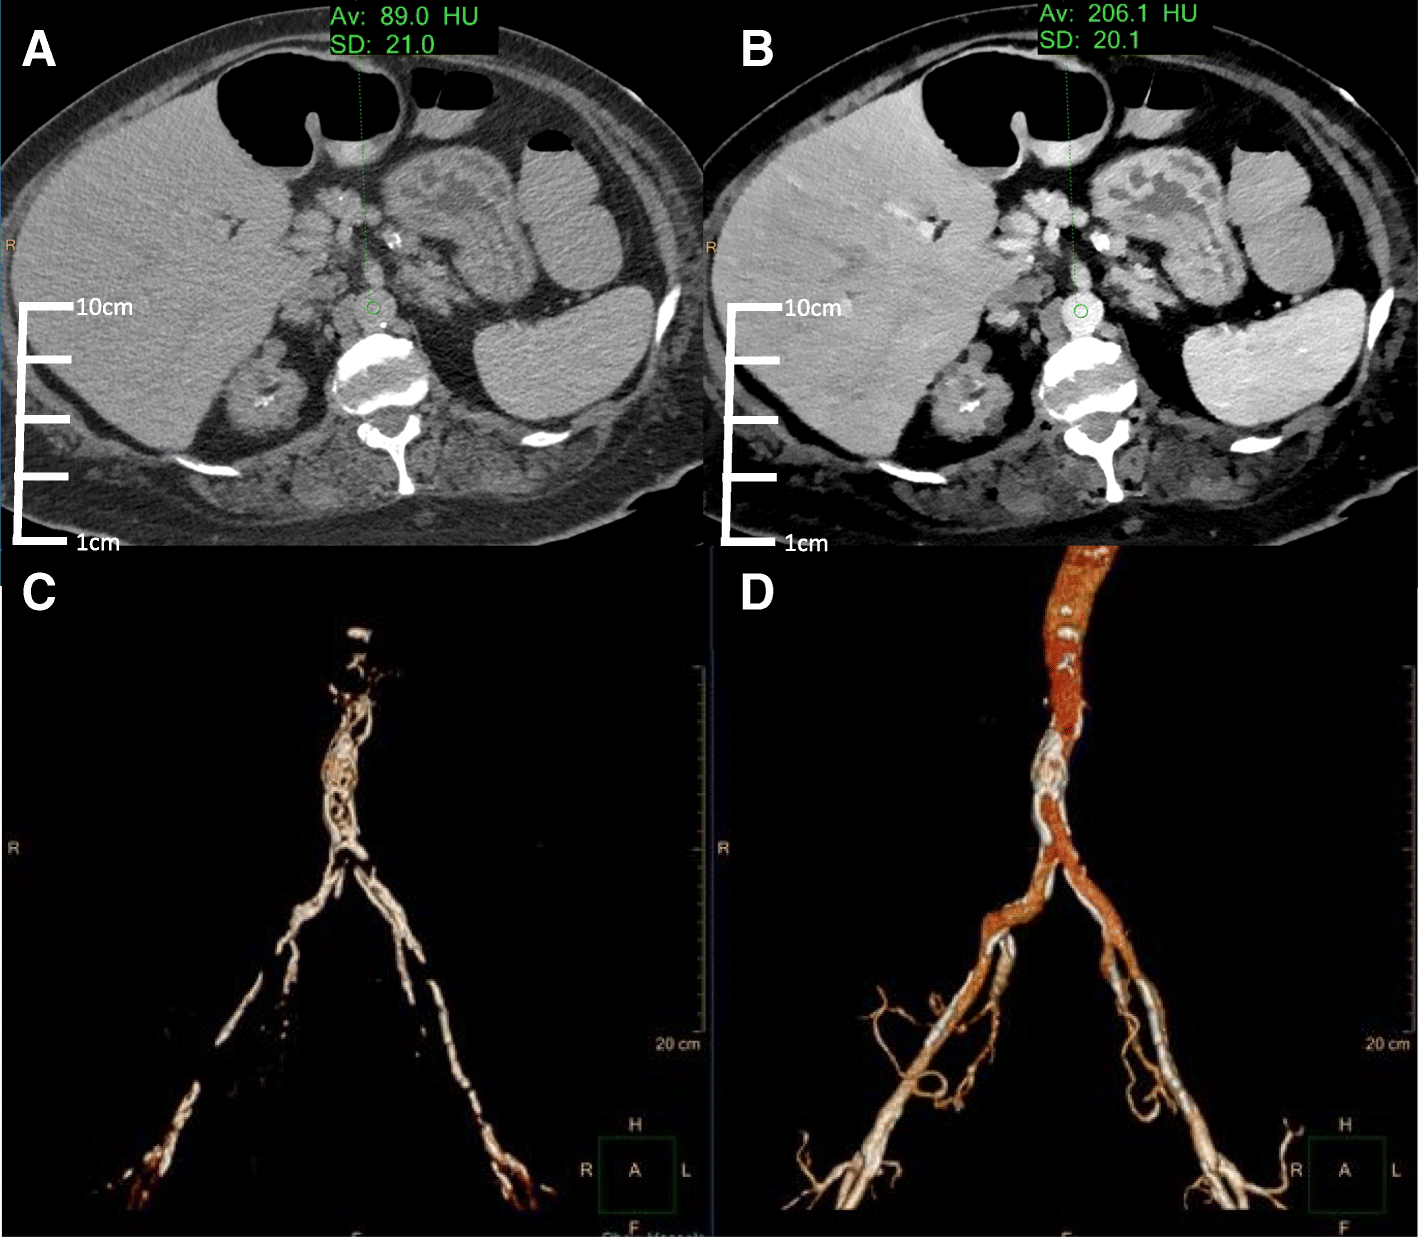

Fig. 1

Conventional (a) and VMI 40 keV (b) axial SDCT images of case 1 TAVR planning. The 40 keV VMI data demonstrates increased aortic vascular contrast enhancement (HU: 206) compared to conventional CT (HU: 89). 3D volume renderings of the abdominal aorta from the conventional (c) and 40 keV VMI (d) data created using the same segmentation tools and workflow show better continuity and inclusion of the vascular lumen on 40 keV VMI compared to conventional CT